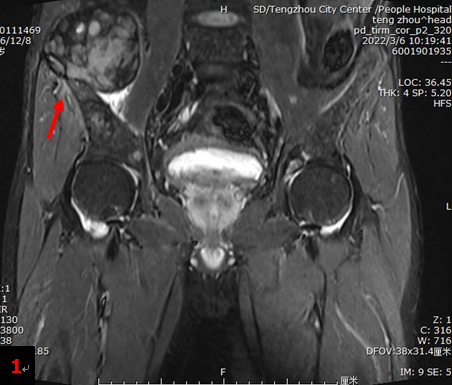

中年男性,一周前外院CT檢查提示:雙腎結(jié)石、雙腎積水、右輸尿管結(jié)石、雙側(cè)髂骨異常。入院后行雙髖關(guān)節(jié)MRI檢查提示:右髂骨翼上方肌肉內(nèi)異常信號(hào)腫塊影,間葉組織來源?(圖1箭)雙側(cè)髂骨翼及雙側(cè)股骨上段異常信號(hào)。為明確病情行18F-FDG PET/CT檢查。

全身多發(fā)骨骼(包括四肢骨和中軸骨)骨質(zhì)破壞(圖2),部分伴軟組織腫塊形成,顯像劑攝取明顯增高,其中右側(cè)髂骨SUVmax約13.0。